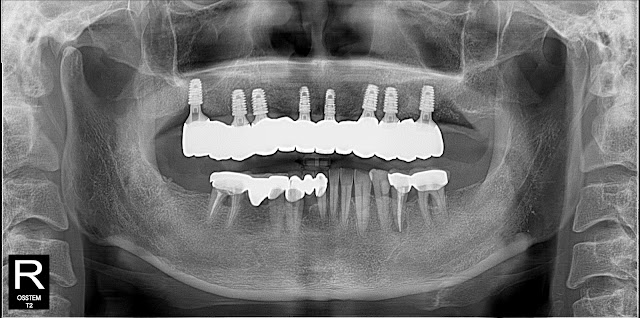

OssteoBionics' SBA implant was placed and submerged.We were able to obtain sufficient initial fixation for fixed temporary prosthesis.To evaluate the bone response of the SBA implant, a two-stage surgery was performed. Autogenous bone, xenogeneic bone, and synthetic bone were transplanted into the surrounding defect area.

This is what it looks like after the second surgery.

The bone response is very good, all bone graft materials used were well maintained around the implant.